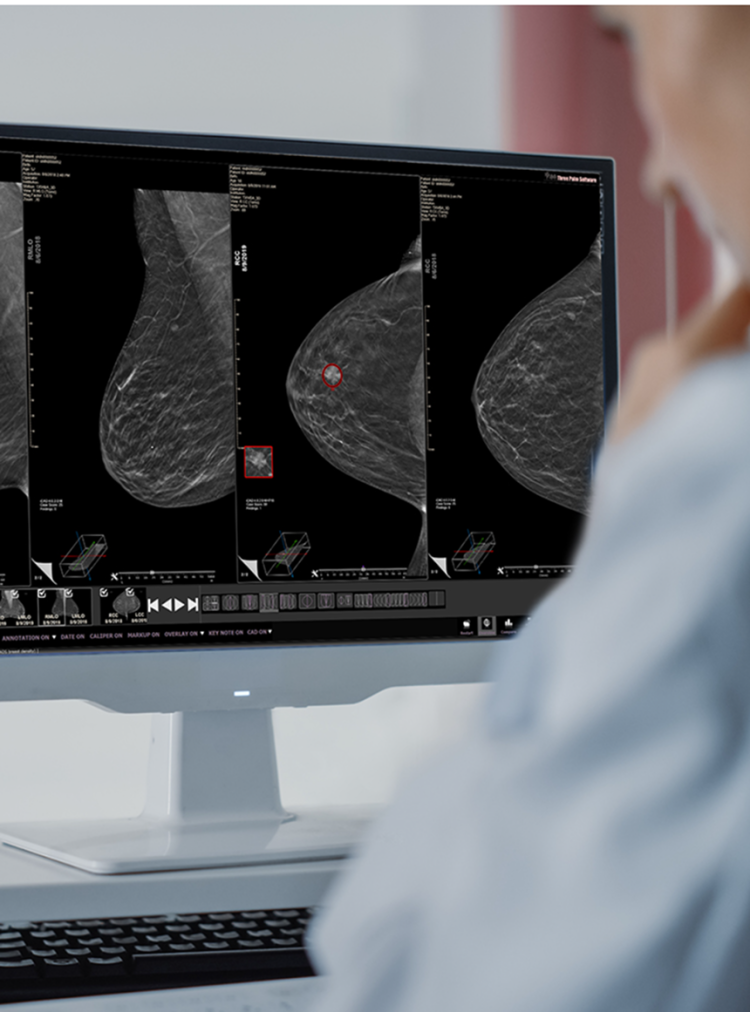

ProFound Detection V4

This next-generation AI solution, trained using advanced deep learning convolutional neural networks (CNN), offers advancements in cancer detection and specificity, achieving a 6.3% improved area under the receiver operating characteristic curve (AUC) over prior version, significantly improving the identification of hard-to-find and aggressive cancers while reducing false positives. This fourth-generation version introduces an option for clinicians to incorporate a prior exam into a current exam’s analysis.

Uncovers hidden cancers feared the most while reducing False Positives.